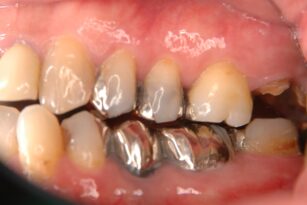

被せ物が取れた 40代 男性 歯牙移植

Before

40代

男性

奥歯の治療

虫歯、歯牙破折

歯牙移植

8回

保険治療なので5000円くらいです。

治療後痛みや腫れが生じることがあります。

術後、激しい運動や治療部位の歯ブラシは禁止になります。

周囲の歯周病の進行状態や歯種によって回復度や成功率が変わります。